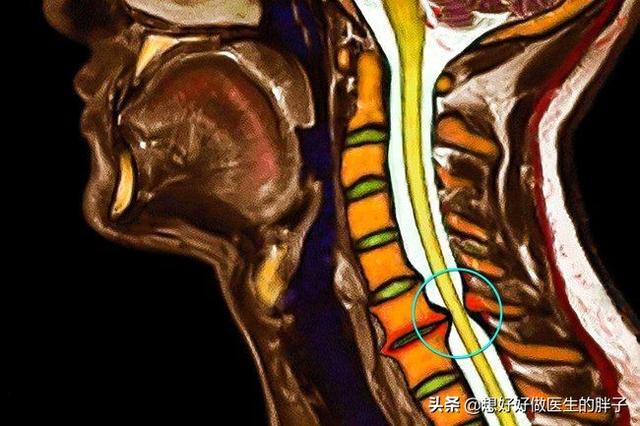

当颈椎出现了键盘突出或者是有骨质增生,导致骨髓形成,压迫到了神经根的时候,就会出现肩部的疼痛,这种疼痛有一种特点,多数是属于像过电那样针刺的疼痛,而且一般与肩部的活动没有相关性,也就是说无论肩膀活动什么样的角度,这种疼痛都存在。反而这种疼痛与颈椎的活动可能会存在一定的关系,比如过度的后仰颈椎或者是向前低头都有可能刺激到神经根,导致疼痛加重。

简单来说就是疼痛表现的肩膀,但是问题在颈椎!

如果是怀疑颈椎导致肩部的疼痛需要进行颈椎核磁检查,明确是否存在颈椎间盘突出或者是骨性结构的异常导致神经受到了卡压,如果伴有肩部或者是上肢的无力,甚至要进行肌电图检查明确神经是否受到了损害。治疗方面可以选择针灸、进行适当的牵引、如果疼痛比较严重可以口服镇痛消炎药、由于这种疼痛多数都导致了神经根的水肿,所以可以口服一些消水肿药物、也可以进行比如经皮神经电刺激等一些物理治疗,一般经过系统的治疗会有缓解。这段时间可能急性期要1~2周的时间,慢慢缓解,大概需要三个月左右的时间吧,所以患者一定要做好心理准备,不要着急,这种问题就是要慢慢来。